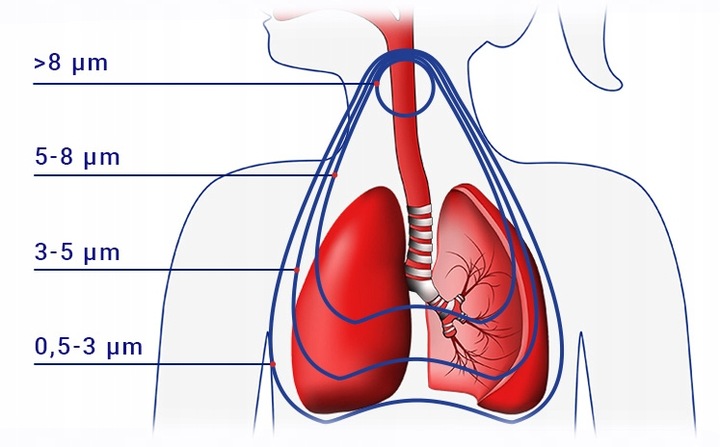

✔️Dwukrotne przyspieszenie nebulizacji bez utraty jakości mgiełki, z MMAD od 2,21 do 2,38 μm i frakcją respirabilną do 84,2%, zapewniając głęboką penetrację leku w układzie oddechowym.

Z frakcją respirabilną do 84,2% i możliwością nebulizacji od 0,29 do 0,65 ml/min, NebulAir+ dostosowuje się do potrzeb dzieci i dorosłych, oferując wygodne maski Soft Touch z ogranicznikiem rozproszenia mgiełki. To więcej niż inhalator – to niezawodny towarzysz w terapii aerozolowej, wspomagający nawilżanie dróg oddechowych i efektywne dostarczanie leków jak sterydy czy antybiotyki.